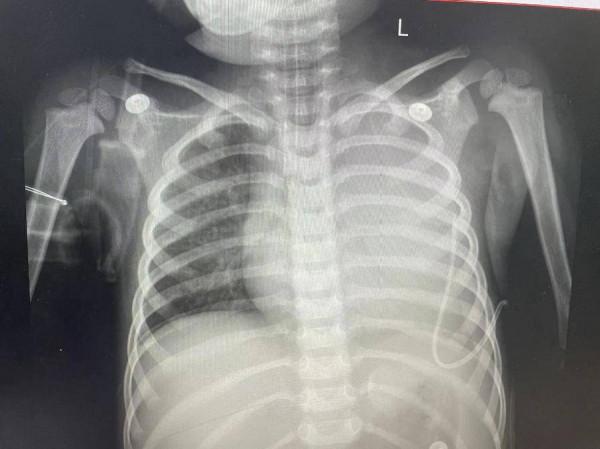

“重症肺炎往往是肺部出現大片狀陰影,肺實變,胸腔積液等。我們遇到過不少病例,都是家長誤把肺炎當作了普通感冒,以至於送到醫院的時候,孩子的肺部感染已經比較嚴重,甚至需要用到呼吸機。”